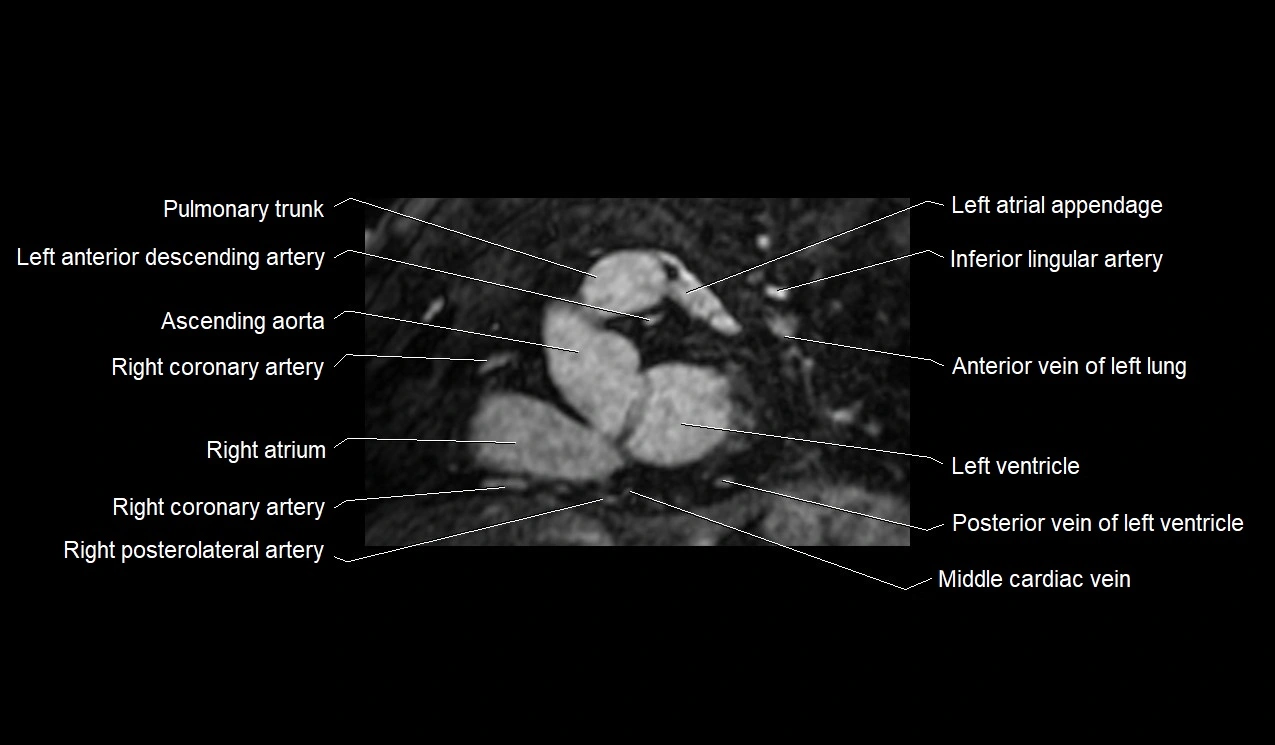

MRI image